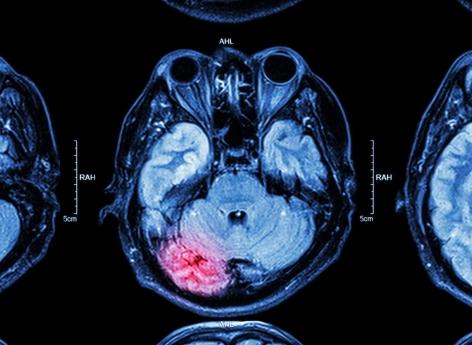

Le gliome est un type rare, mais agressif, de cancer au cerveau. Il survient dans les cellules gliales telles que les astrocytes. Ces dernières sont pourtant considérées comme "moins susceptibles de provoquer des tumeurs", expliquent les chercheurs du University College London Cancer Institute dans un communiqué. "Cependant, des découvertes récentes ont démontré qu'après une blessure, les astrocytes peuvent à nouveau présenter un comportement de cellule-souche", plus sujets à devenir cancéreuses, remarquent-ils.

Traumatisme crânien : un risque de tumeur cérébrale 4 fois plus élevé

Pour vérifier son hypothèse, l'équipe a consulté les dossiers médicaux de plus de 20.000 patients ayant eu des lésions cérébrales traumatiques. Les chercheurs ont constaté que les personnes qui avaient subi une blessure à la tête, étaient près de quatre fois plus susceptibles de développer un cancer du cerveau plus tard par rapport aux individus non blessés.